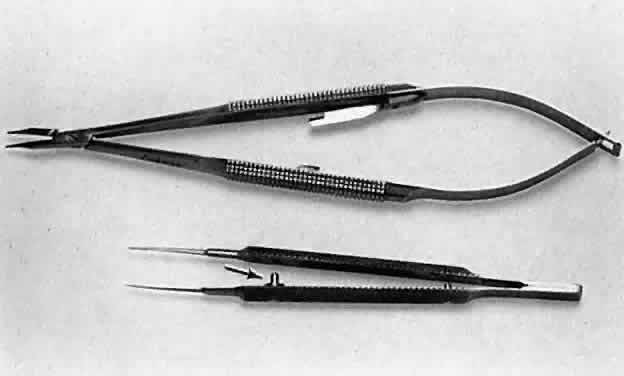

Frequently, the beginning surgeon complains that an instrument does not

hold a fine suture, such as 10-0 nylon. Often, this problem results from

improper handling of the instrument. For example, the design of a

surgical tie calls for the surgeon to apply pressure at the flat serrated

handle to ensure that the tying platforms meet properly. If a torque

or oblique force is applied to the tying forceps, the 10-0 nylon may

be inadvertently sheared or may not be grasped tightly. To avoid this

problem, various instruments have a guide incorporated into the handle. The

guide requires proper alignment for the instrument to close (Fig. 13). The same difficulty may be encountered when using a locking needle holder. The

lock will hold only if the needle holder is positioned properly

within the surgeon's fingertips and the force applied is not

oblique to the handle. If the forces applied to the instruments exceed

those provided for in its construction, the components of the instrument

will bend and the jaws will not appose correctly (Fig. 14).4 Instruments have been designed to be held at the serrated portion of the

handle. Holding them more anteriorly or posteriorly alters the force

applied and may result in malfunctioning of the instrument.  Fig. 13. A surgical tie is shown on the bottom. A guide is incorporated into the

handle (arrow). The guide ensures proper alignment for the instrument to close. On the

top, a locking needle holder is shown. The lock will hold only if the

needle holder is positioned properly in the surgeon's fingertips

and the force applied is not oblique to the handle. Fig. 13. A surgical tie is shown on the bottom. A guide is incorporated into the

handle (arrow). The guide ensures proper alignment for the instrument to close. On the

top, a locking needle holder is shown. The lock will hold only if the

needle holder is positioned properly in the surgeon's fingertips

and the force applied is not oblique to the handle.